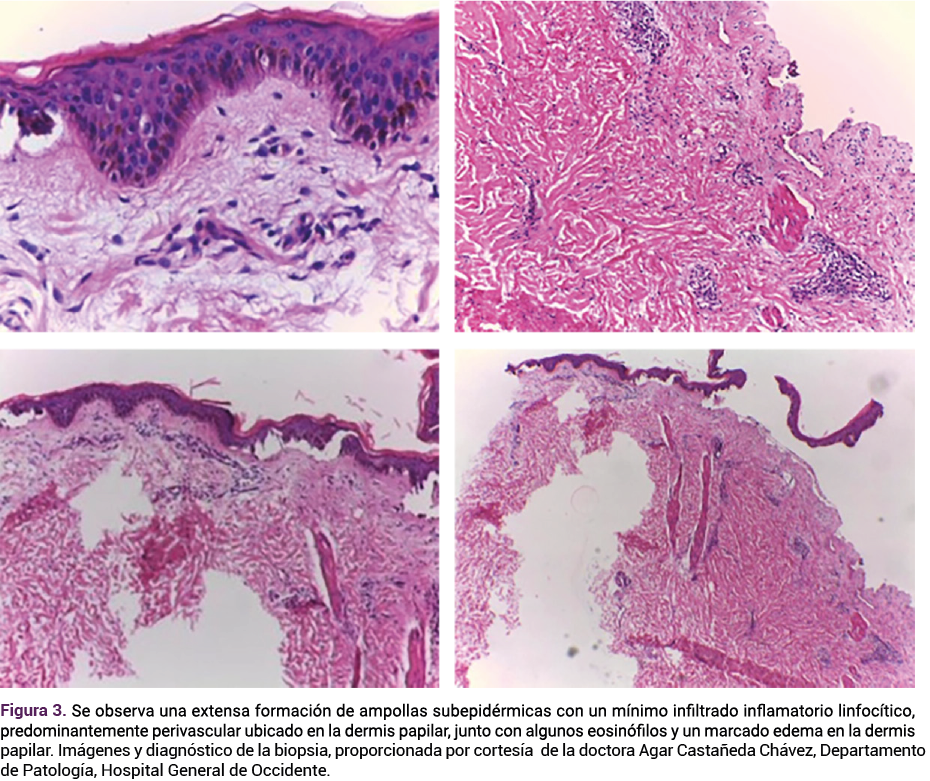

Dos días después, el informe de la biopsia confirmó el diagnóstico de penfigoide gestacional (Figura 3). La mejoría clínica de las lesiones se observó cinco días después del inicio del tratamiento por lo que se fue disminuyendo la dosis de tratamiento sistémico; el alivio completo se produjo dos semanas después.

<strong>Figura 3</strong>

Figura 3. Hallazgos histopatológicos compatibles con penfigoide gestacional, con separación subepidérmica y patrón inflamatorio sugerente.

El diagnóstico se fundamenta en el cuadro dermatológico, el estudio histopatológico de la lesión o, bien, en estudios de inmunofluoresencia directa; todos ayudan a diferenciarlo de otras dermatosis características en el embarazo.4 Lo que se encuentre en los estudios histológicos dependerá de la intensidad y la evolución de las lesiones, la abundancia de eosinófilos será constante en esta enfermedad.4 Sin embargo, la clave del diagnóstico será la formación de ampollas subepidérmicas en la membrana basal.4 En la totalidad de los análisis mediante inmunoflourescencia directa se apreciará un depósito lineal de C3 a lo largo de la membrana basal.4 Con estas características y el cuadro clínico podrá distinguirse de otras enfermedades.4 Entre sus diagnósticos diferenciales se encuentran: erupción papular pruriginosa en placas del embarazo, eritema secundario a fármacos, dermatosis lineal por depósito de IgA y penfigoide bulloso.4